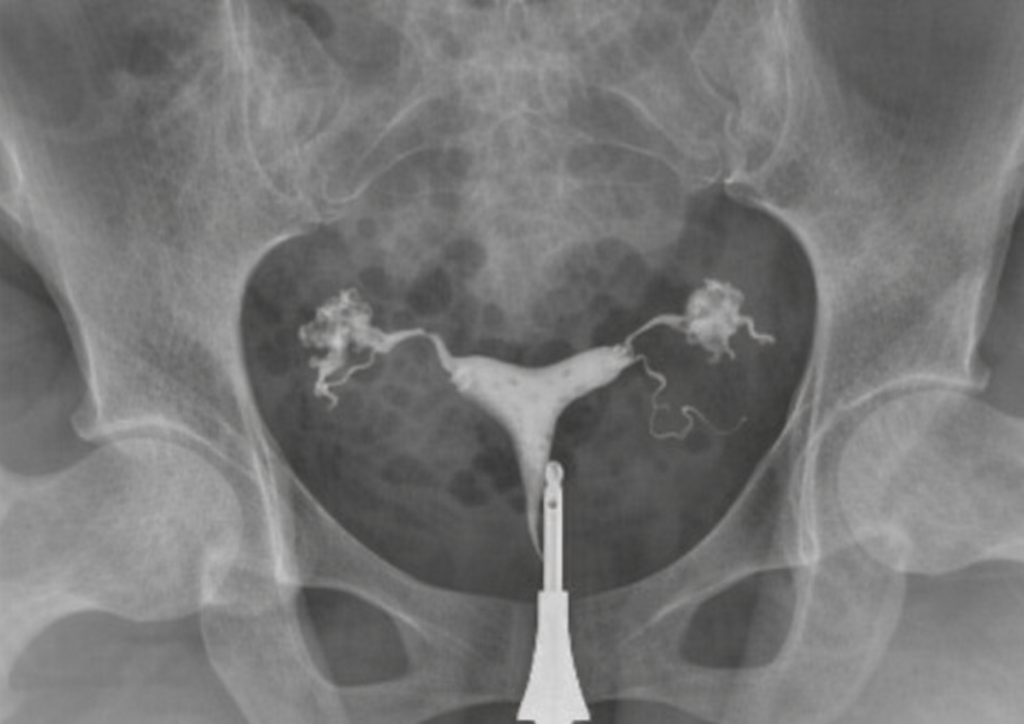

Wiedereröffnung Der Eileiter